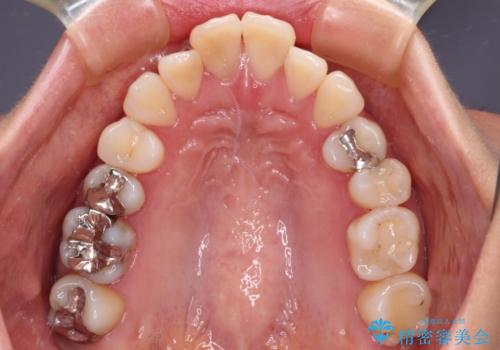

- 八重歯と上の前歯が出っ歯になっていることを気にして来院された患者様です。

横から見た際の口元の飛び出した印象も改善したいとのことで、上下左右の第一小臼歯4本を抜歯し、ワイヤー装置にて抜歯矯正を行うこととしました。

前歯の変色している歯は、神経組織が壊死していたため、矯正治療前に根管治療を実施し、矯正治療後にオールセラミッククラウンにて補綴治療を行うこととしました。